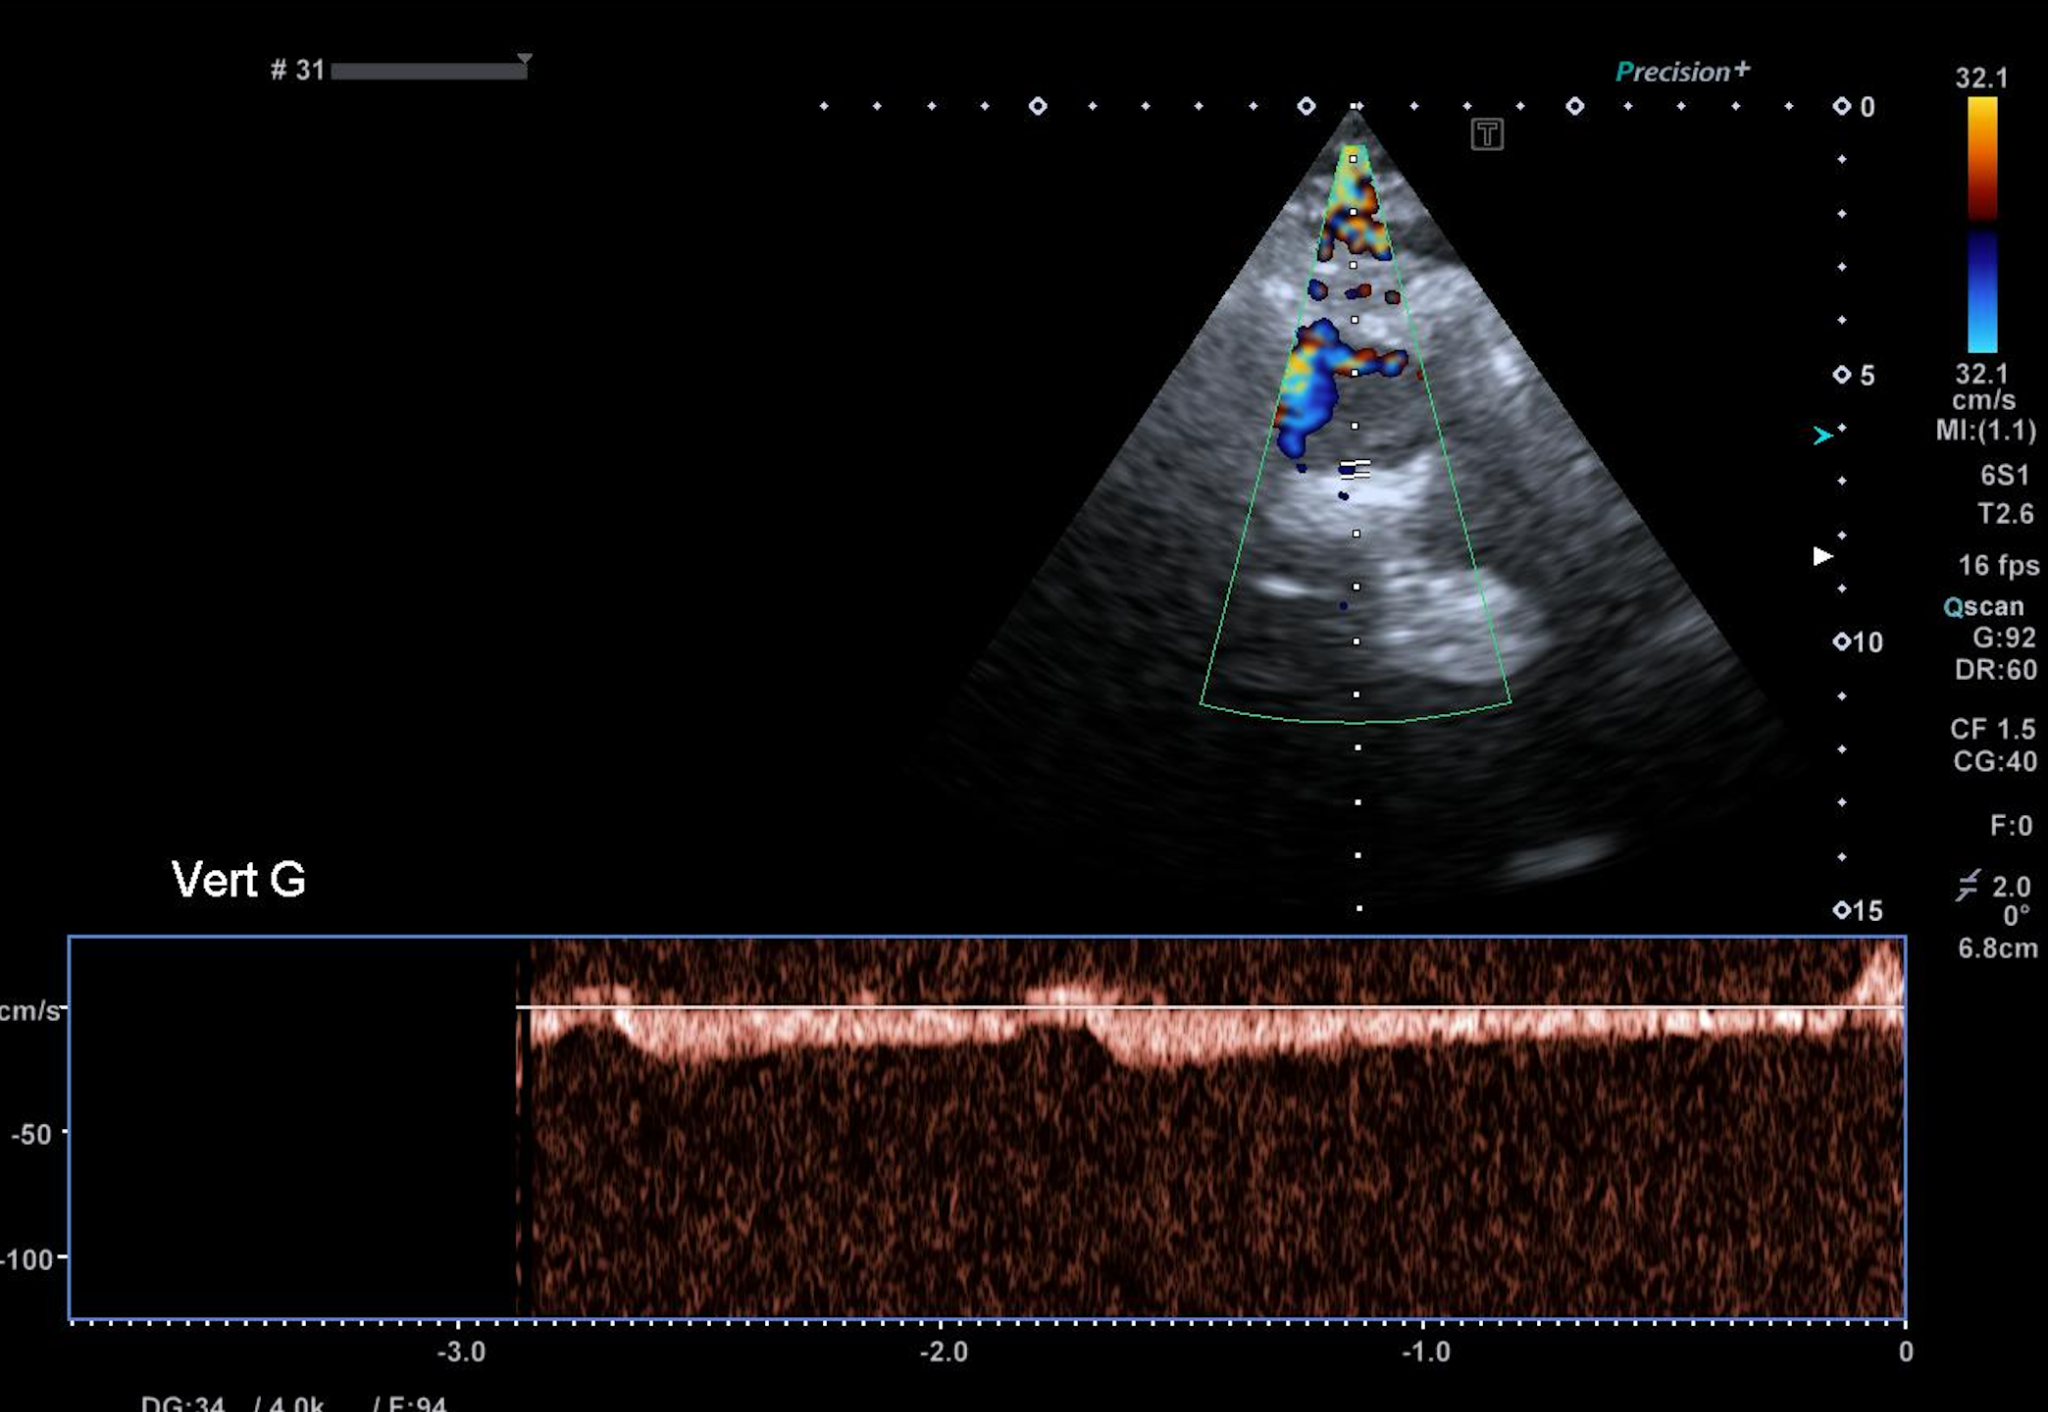

Il existe cependant un retentissement sur l’artère vertébrale gauche, avec un vol vertébro sous clavier intermittent : inversion uniquement du flux systolique.

Dans les cas plus évolués, l’inversion est systolo diastolique (vol permanent).

Au repos, on retrouve un retentissement en intracrânien en V4 un tracé similaire que sur  l’artère vertébrale en V2. Il n’existe pas de retentissement sur le tronc basilaire, bien compensé par la vertébrale controlatérale.